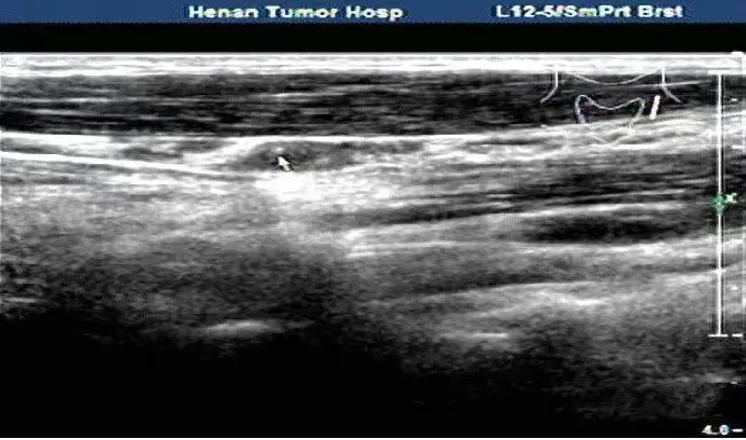

病例:右侧颈部肿痛3天,颈部可触及多个痛性结节。

超声描述:右侧颈部Ⅲ、Ⅳ区可见多发肿大的淋巴结,大者约21x6mm,呈椭圆形,皮质增厚,髓质居中,内部血流信号明显增多,呈放射状分布。